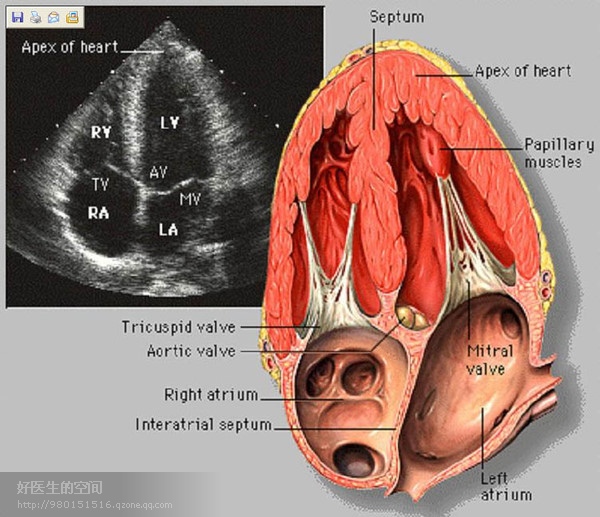

经典心脏超声切面图及解剖标示